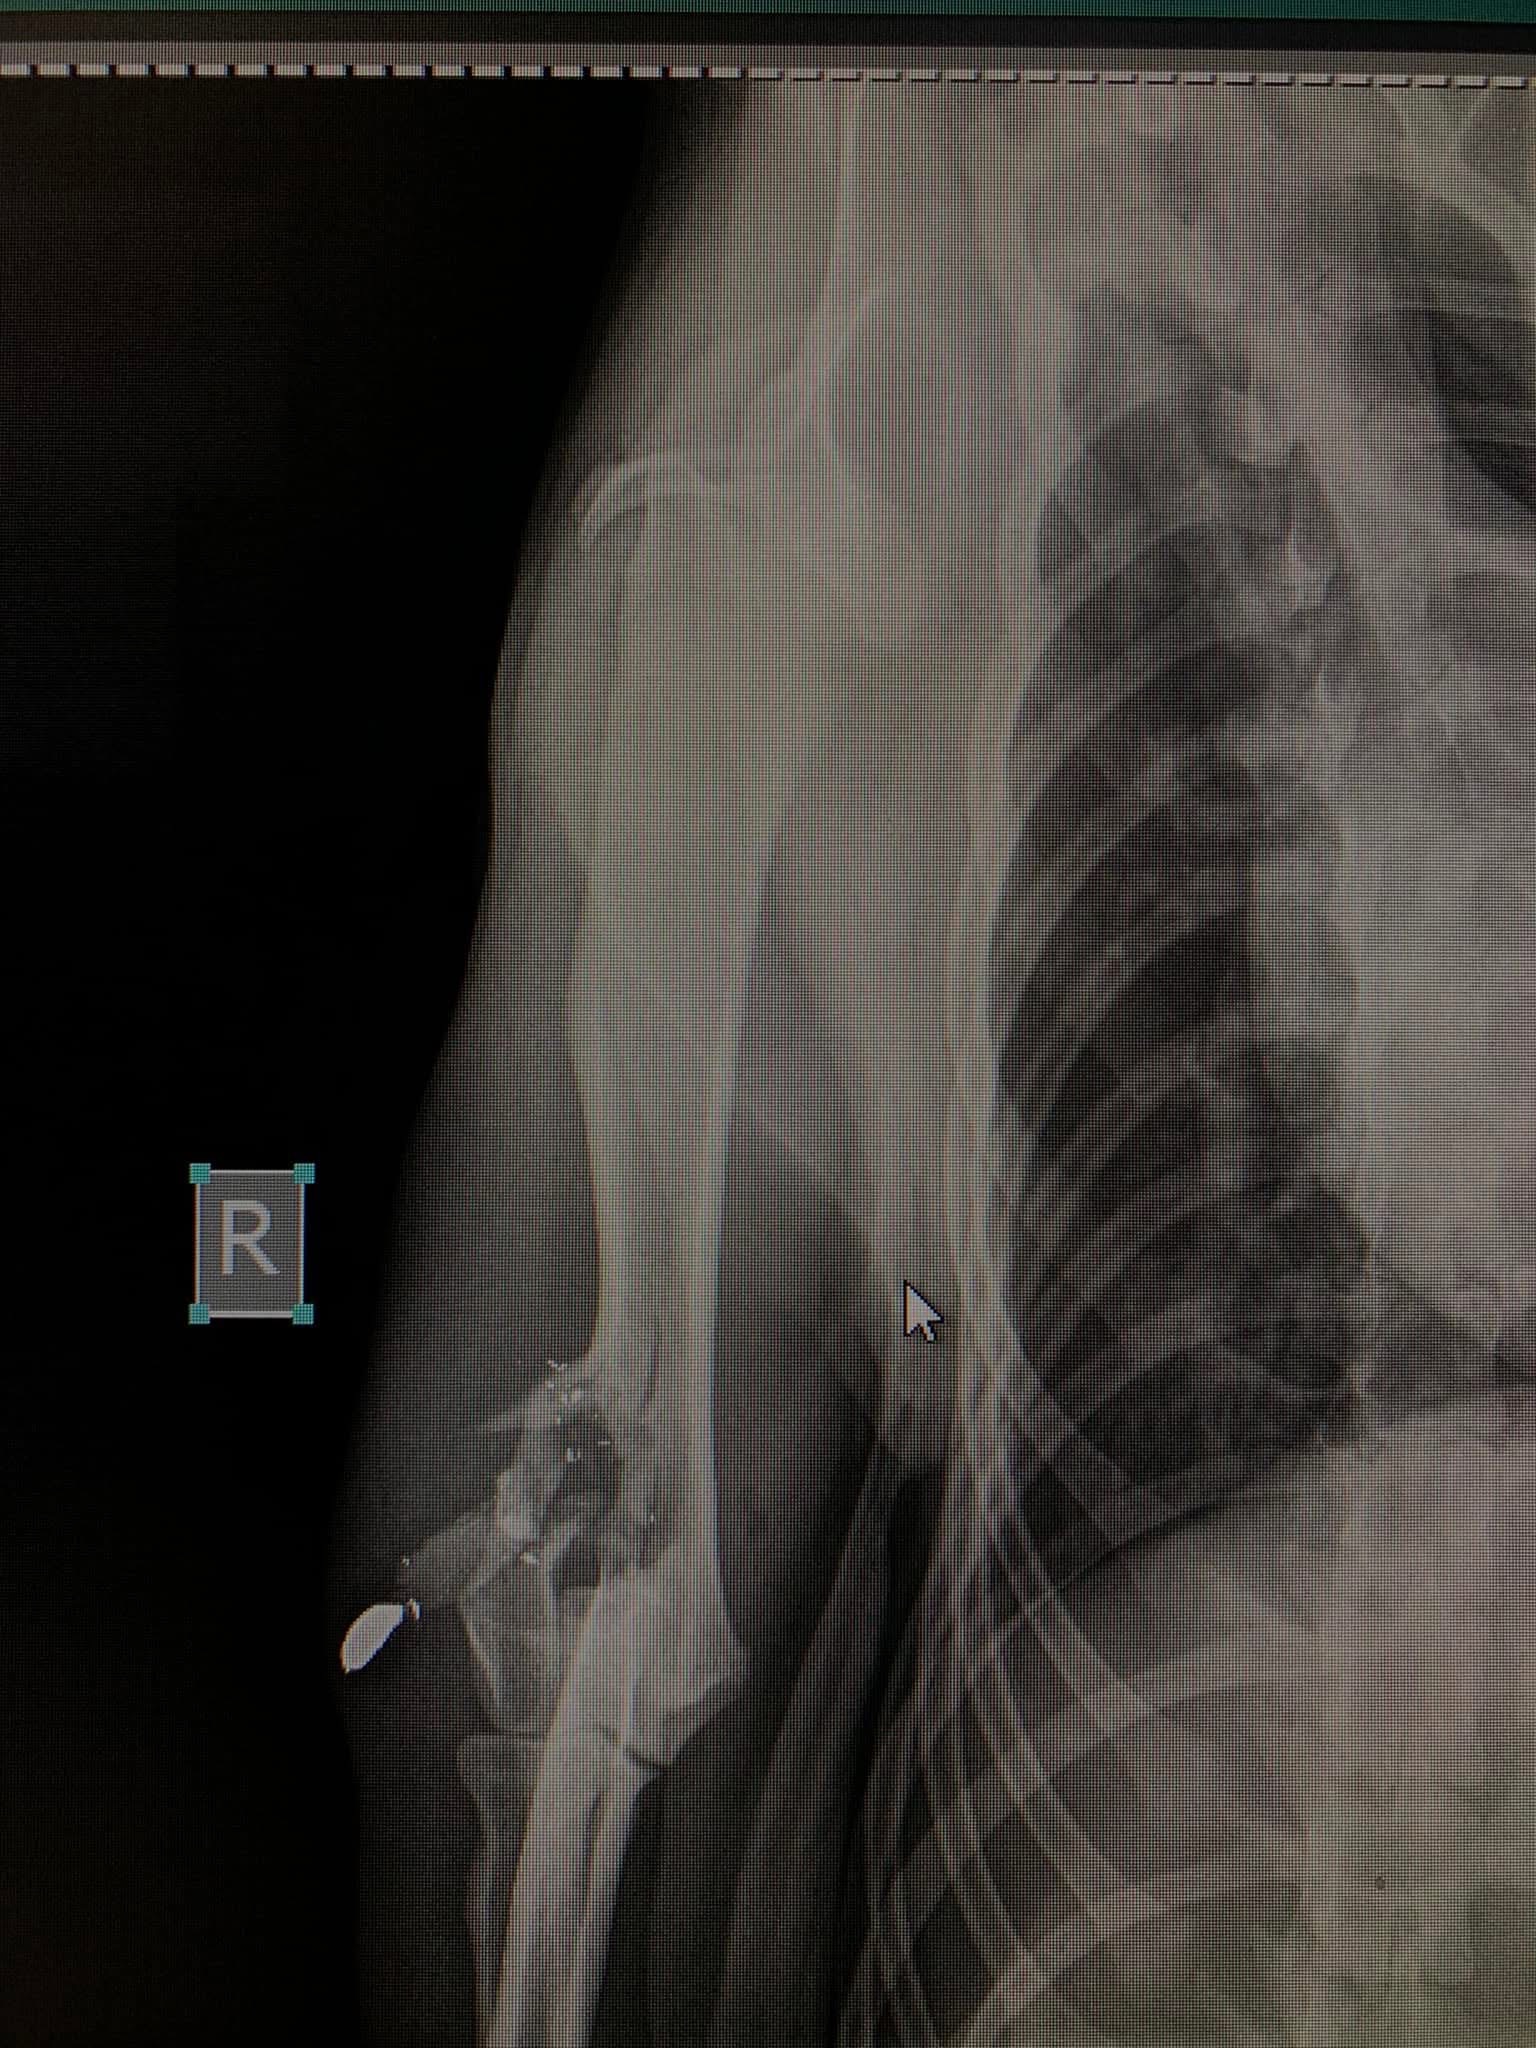

Psi i mačke su aktivne životinje sklone ortopedskim povredama, a najčešći uzroci su saobraćajne nesreće, padovi, udarci.

Genetika i degenerativni procesi često igraju ključne uloge u razvoju različitih problema sa kostima, zglobovima, ligamentima i hrskavicom, što može biti prisutno od rođenja ili se razvija tokom rasta životinje. Ortopedske povrede ozbiljno utiču na kvalitetu života ljubimaca, ali uz pravovremenu dijagnozu i terapiju se mogu uspješno oporaviti.

- Liječenje prijeloma kostiju, uključujući intraartikularne frakture